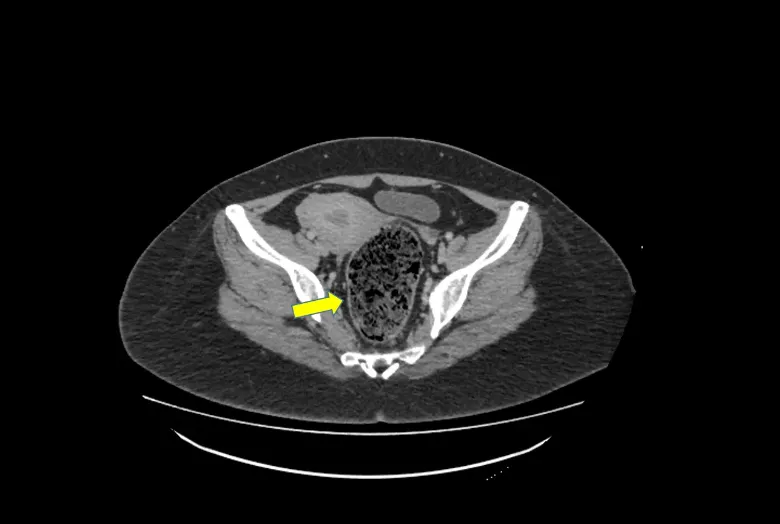

Figure 6: Case of acute constipation with severe abdominal pain in a young lady – CT scan of the abdomen and pelvis revealed impacted stools with gas shadowing (yellow arrow), classical for fecal matter. Patients often present in the emergency department out of severe pain and has often tried numerous remedies be it, over-the-counter painkillers or laxatives, and visited her GP several times for analgesic injections.